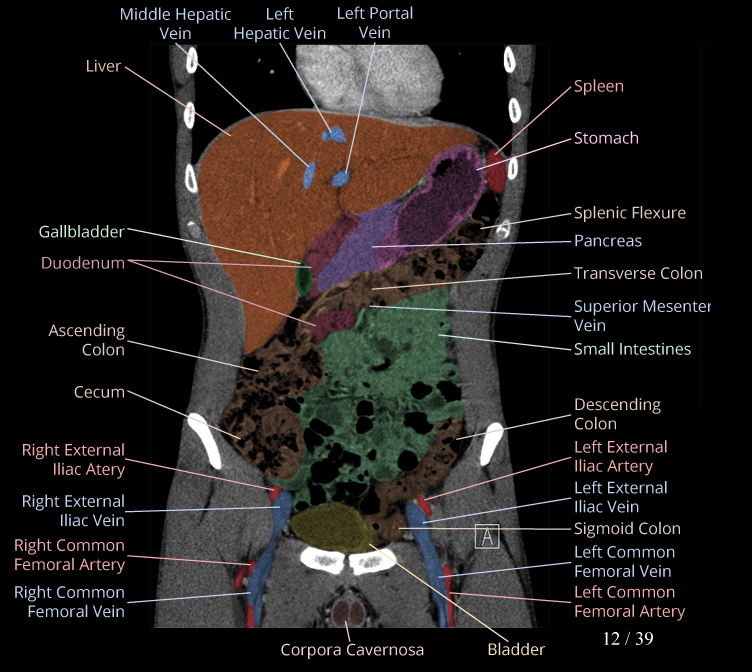

Body

Covers abdominal CT anatomy.